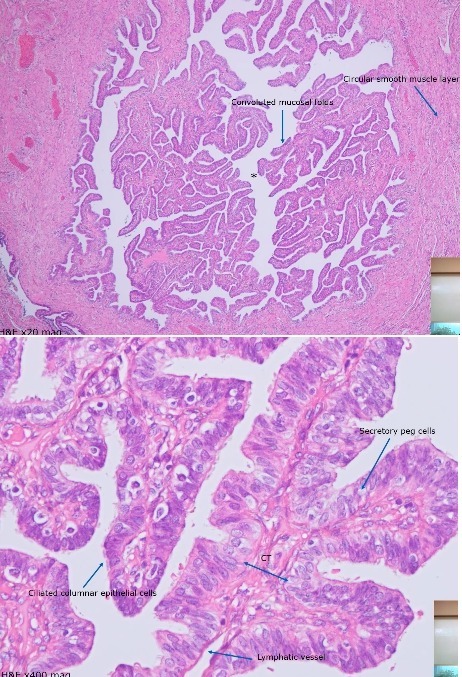

Fallopian Tube

A

Mucosa made up of complex folds

Ciliated columnar epithelium (not all ciliated)

Secretory peg cells seen within epithelium

CT framework that makes up the folds

Smooth muscle layer (circular and longitudinal) outside of mucosal folds